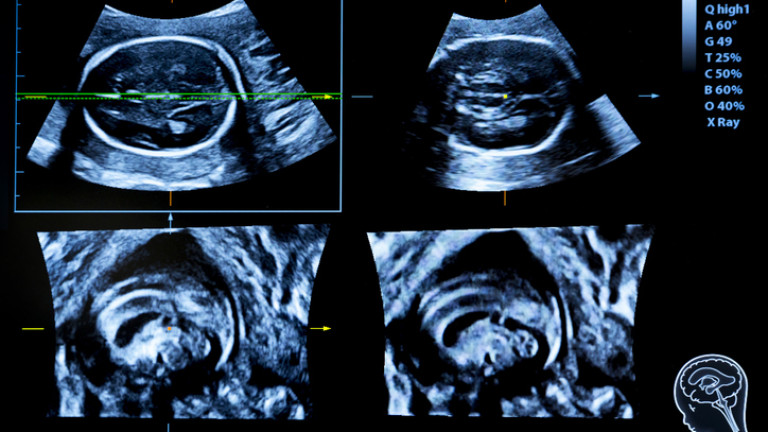

Пет месеца след трансплантацията, екипът на д-р Ейзенберг пише - матката не показва признаци на отхвърляне, ултразвуковите изследвания са нормални и получателят е имал редовна менструация. Предварително оплодените и замразените яйцеклетки на 32-годишната жена са имплантирани след седем месеца, а 10 дни по-късно тя е с потвърдена бременна.